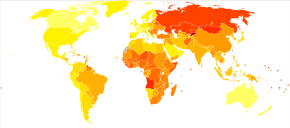

Epidemiology

Worldwide, it is estimated there are 31 million stroke survivors, though about 6 million deaths were due to cerebrovascular disease (2nd most common cause of death in the world and 6th most common cause of disability).[26]

Cerebrovascular disease primarily occurs with advanced age; the risk for developing it goes up significantly after 65 years of age. CVD tends to occur earlier than Alzheimer's Disease (which is rare before the age of 80). In some countries such as Japan, CVD is more common than AD.

In 2012 6.4 million US individuals (adults) had a stroke, which corresponds to 2.7% in the U.S. With approximately 129,000 deaths in 2013 (U.S.)[27]

Geographically, a "stroke belt" in the US has long been known, similar to the "diabetes belt"which includes all of Mississippi and parts of Alabama, Arkansas, Florida, Georgia, Kentucky, Louisiana, North Carolina, Ohio, Pennsylvania, South Carolina, Tennessee, Texas, Virginia, and West Virginia.[28]